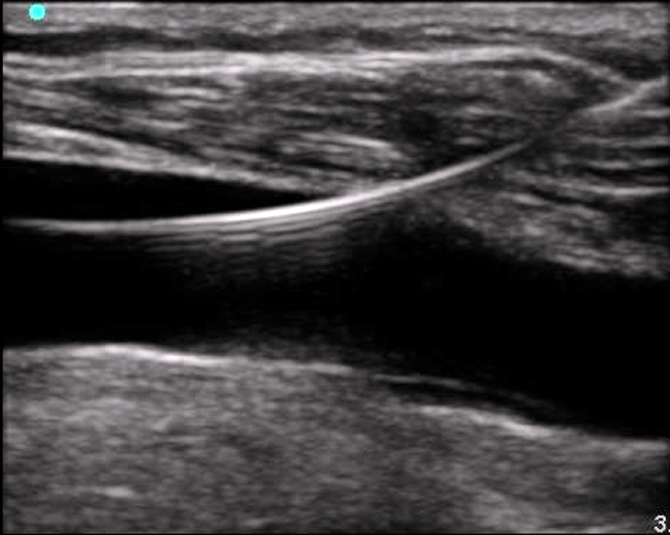

When using ultrasound to evaluate for a pneumothorax, the probe is usually placed on the anterior chest in the 2nd-4th intercostal space & midclaviular line.

This is a starting point and a likely place to find a pneumothorax when the patient is in the supine position. Move up 1-2 rib spaces...medially...and laterally.

A high frequency linear probe is ideal for this exam.

Decrease the depth setting, so that the ultrasound image shows a maximum depth of about 4 cm. The probe is placed in a longitudinal position with the marker-dot pointed cephalad/towards the head

In this orientation rib shadows can be used to find the pleural plane. It is best to adjust the probe linearly until two ribs are apparent, one on each side of the image.

Between the ribs the pleural interface will be apparent at the posterior border of the ribs. It is important to anchor the probe and hold it very still while looking for the sliding motion of the visceral pleura against the parietal pleura.

" Walking Ants " & "Comet tails" (reverberation artefact) may also be present, confirming normal lung.

Change the mode to M-mode.

Normal sliding pleura and lung interface should look like 'wave crashing romantically on a pacific island beach' "SEA-SHORE SIGN"

A PTX will lack normal lung sliding / Ants / Comet tails & have the "Stratosphere sign" on M Mode